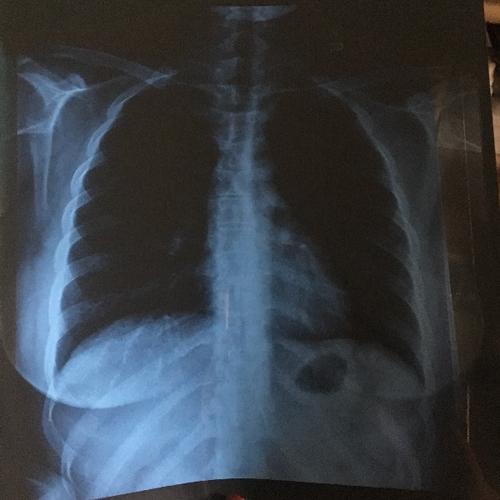

做x胸片多久可以怀孕

拍片子后多久可以怀孕,这是很多人比较关心的问题。拍片后,有很多人关心对方的时间。因为拍片后是需要注意一些事项的。那么,拍片子后多久可以怀孕呢?接下来,小编就为大家详细介绍一下这方面的内容。